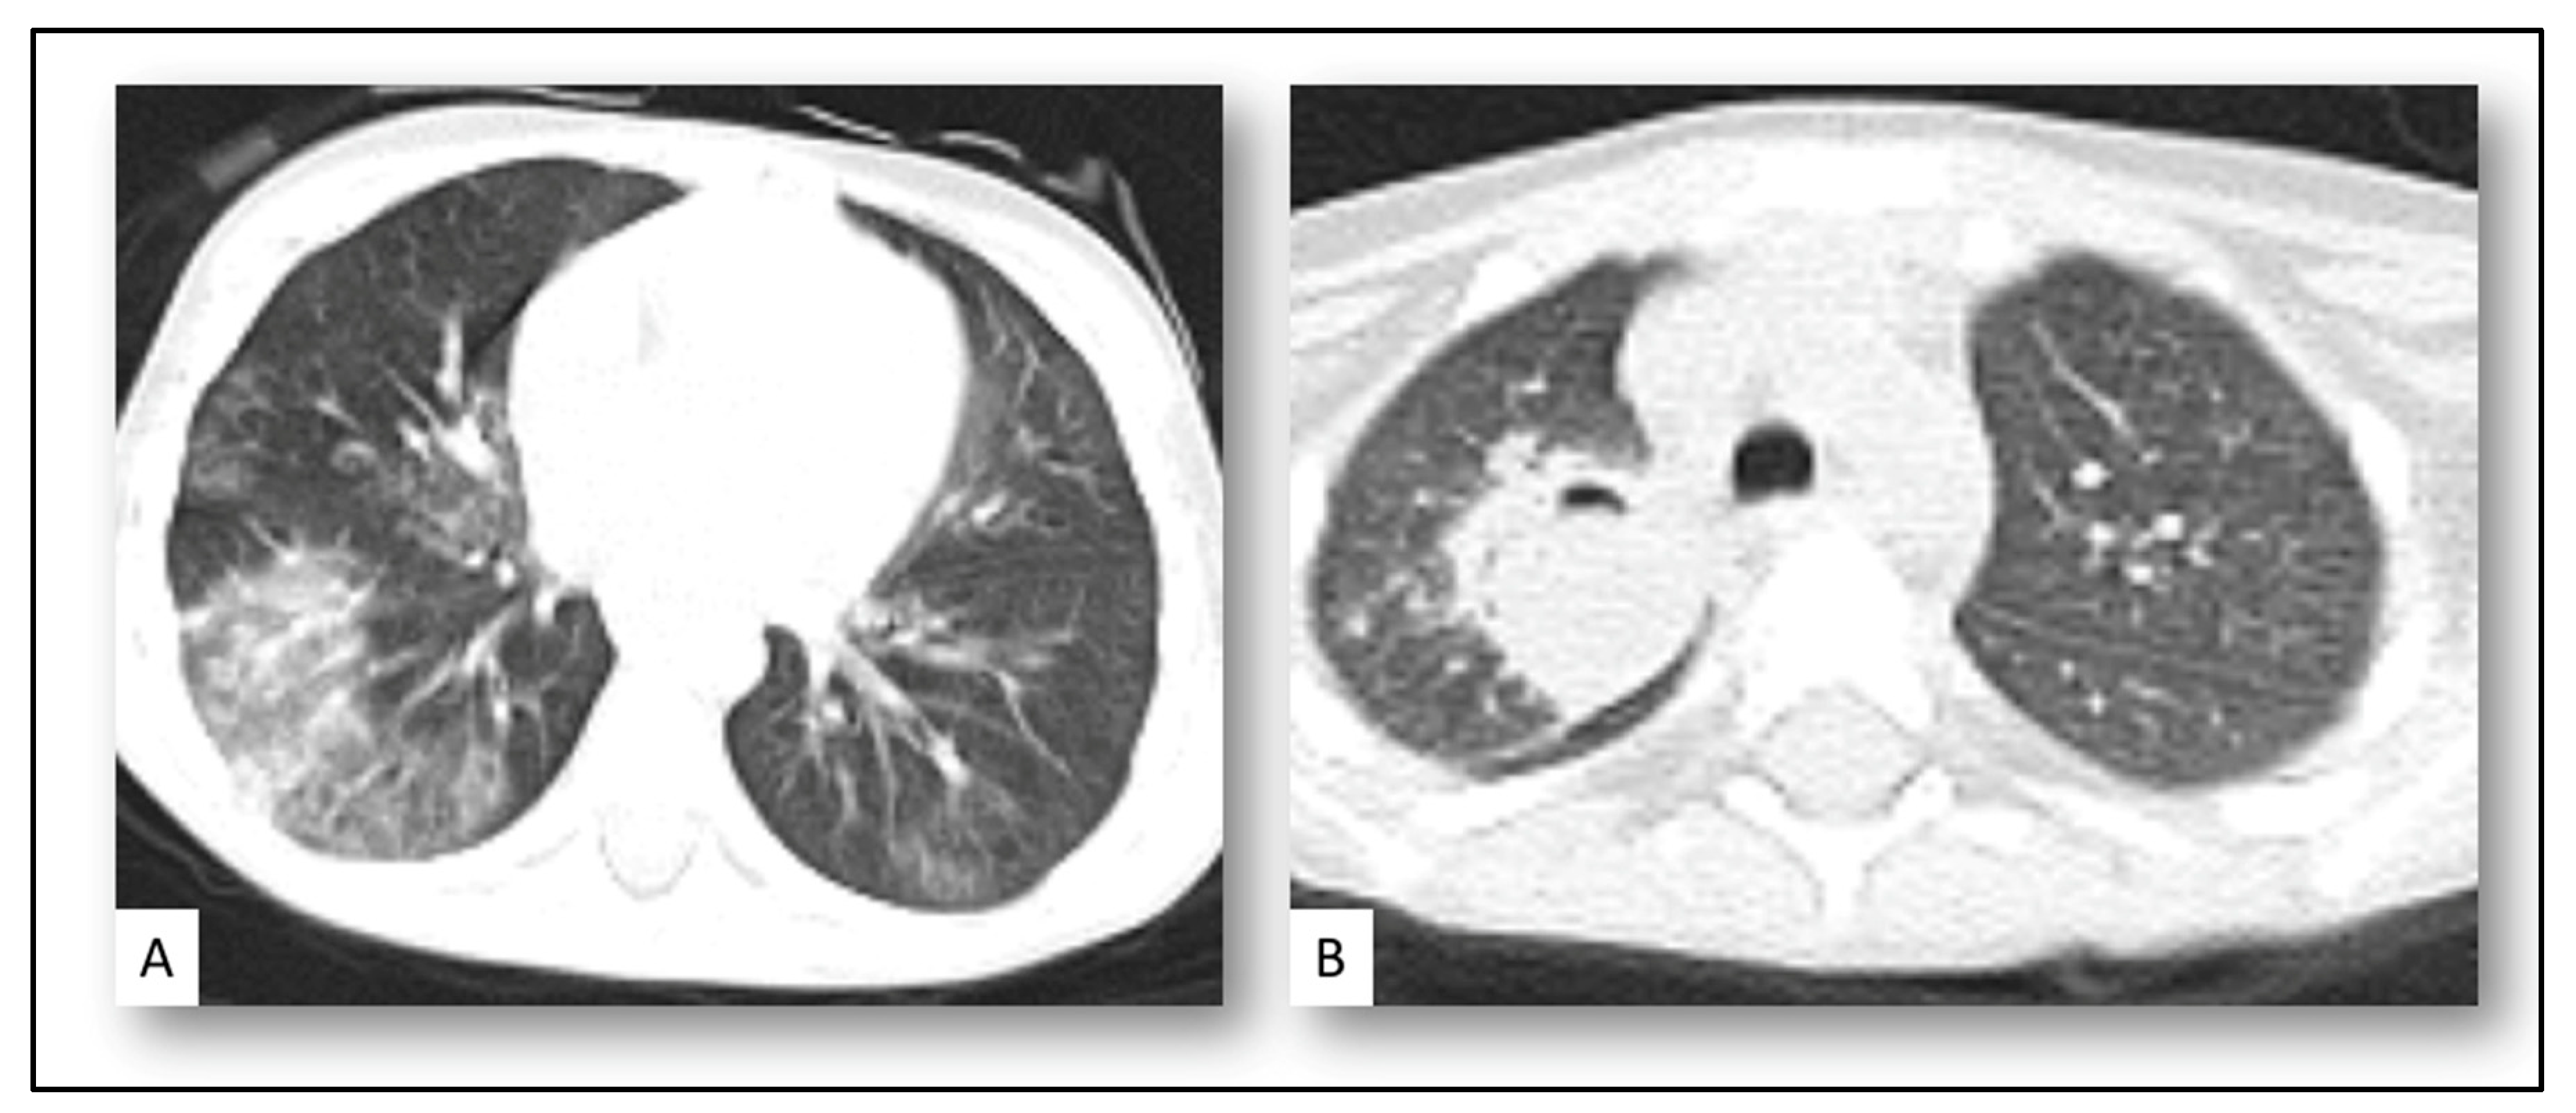

| - Pulmonary nodule with halo sign | 11 (52%) |

| - Pyramidal consolidation patch | 4 (20%) |

| - Cavitary lung lesion | 6 (28%) |